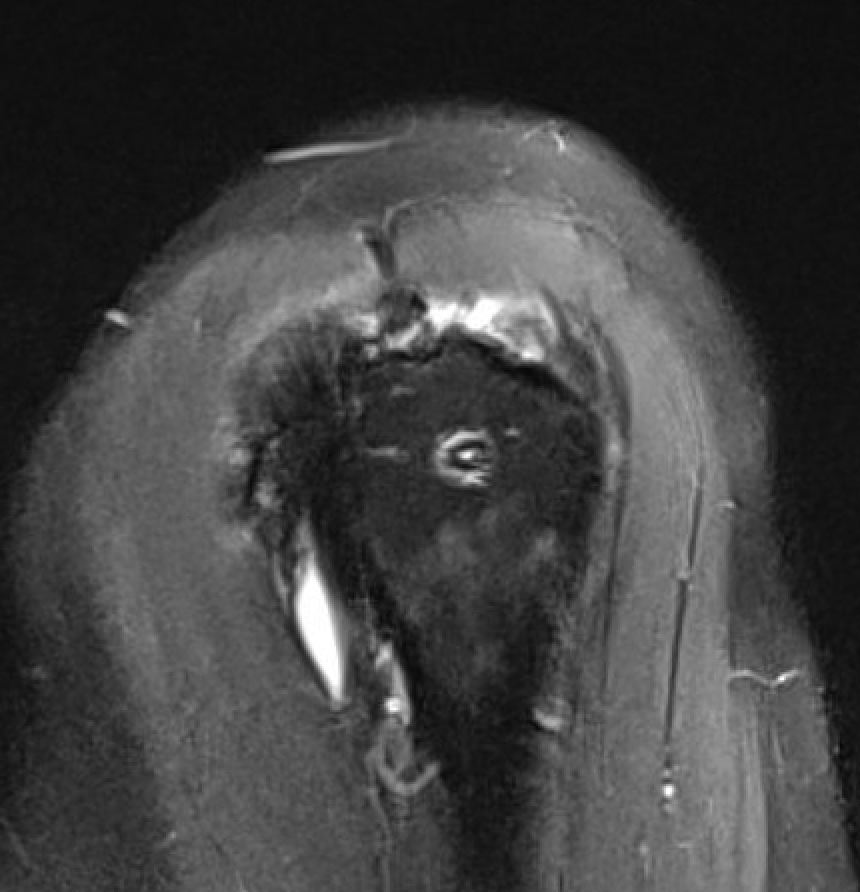

Retear

retearretearretear

Retearretear

Presentation

Pain / stiffness / weakness

Incidence